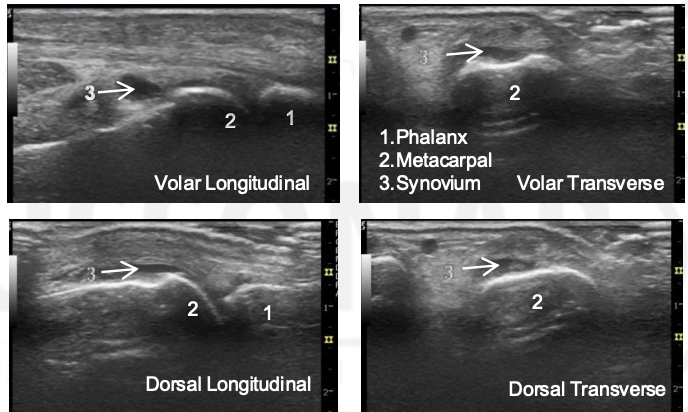

What is the arrow pointing to?

Synovial Distension